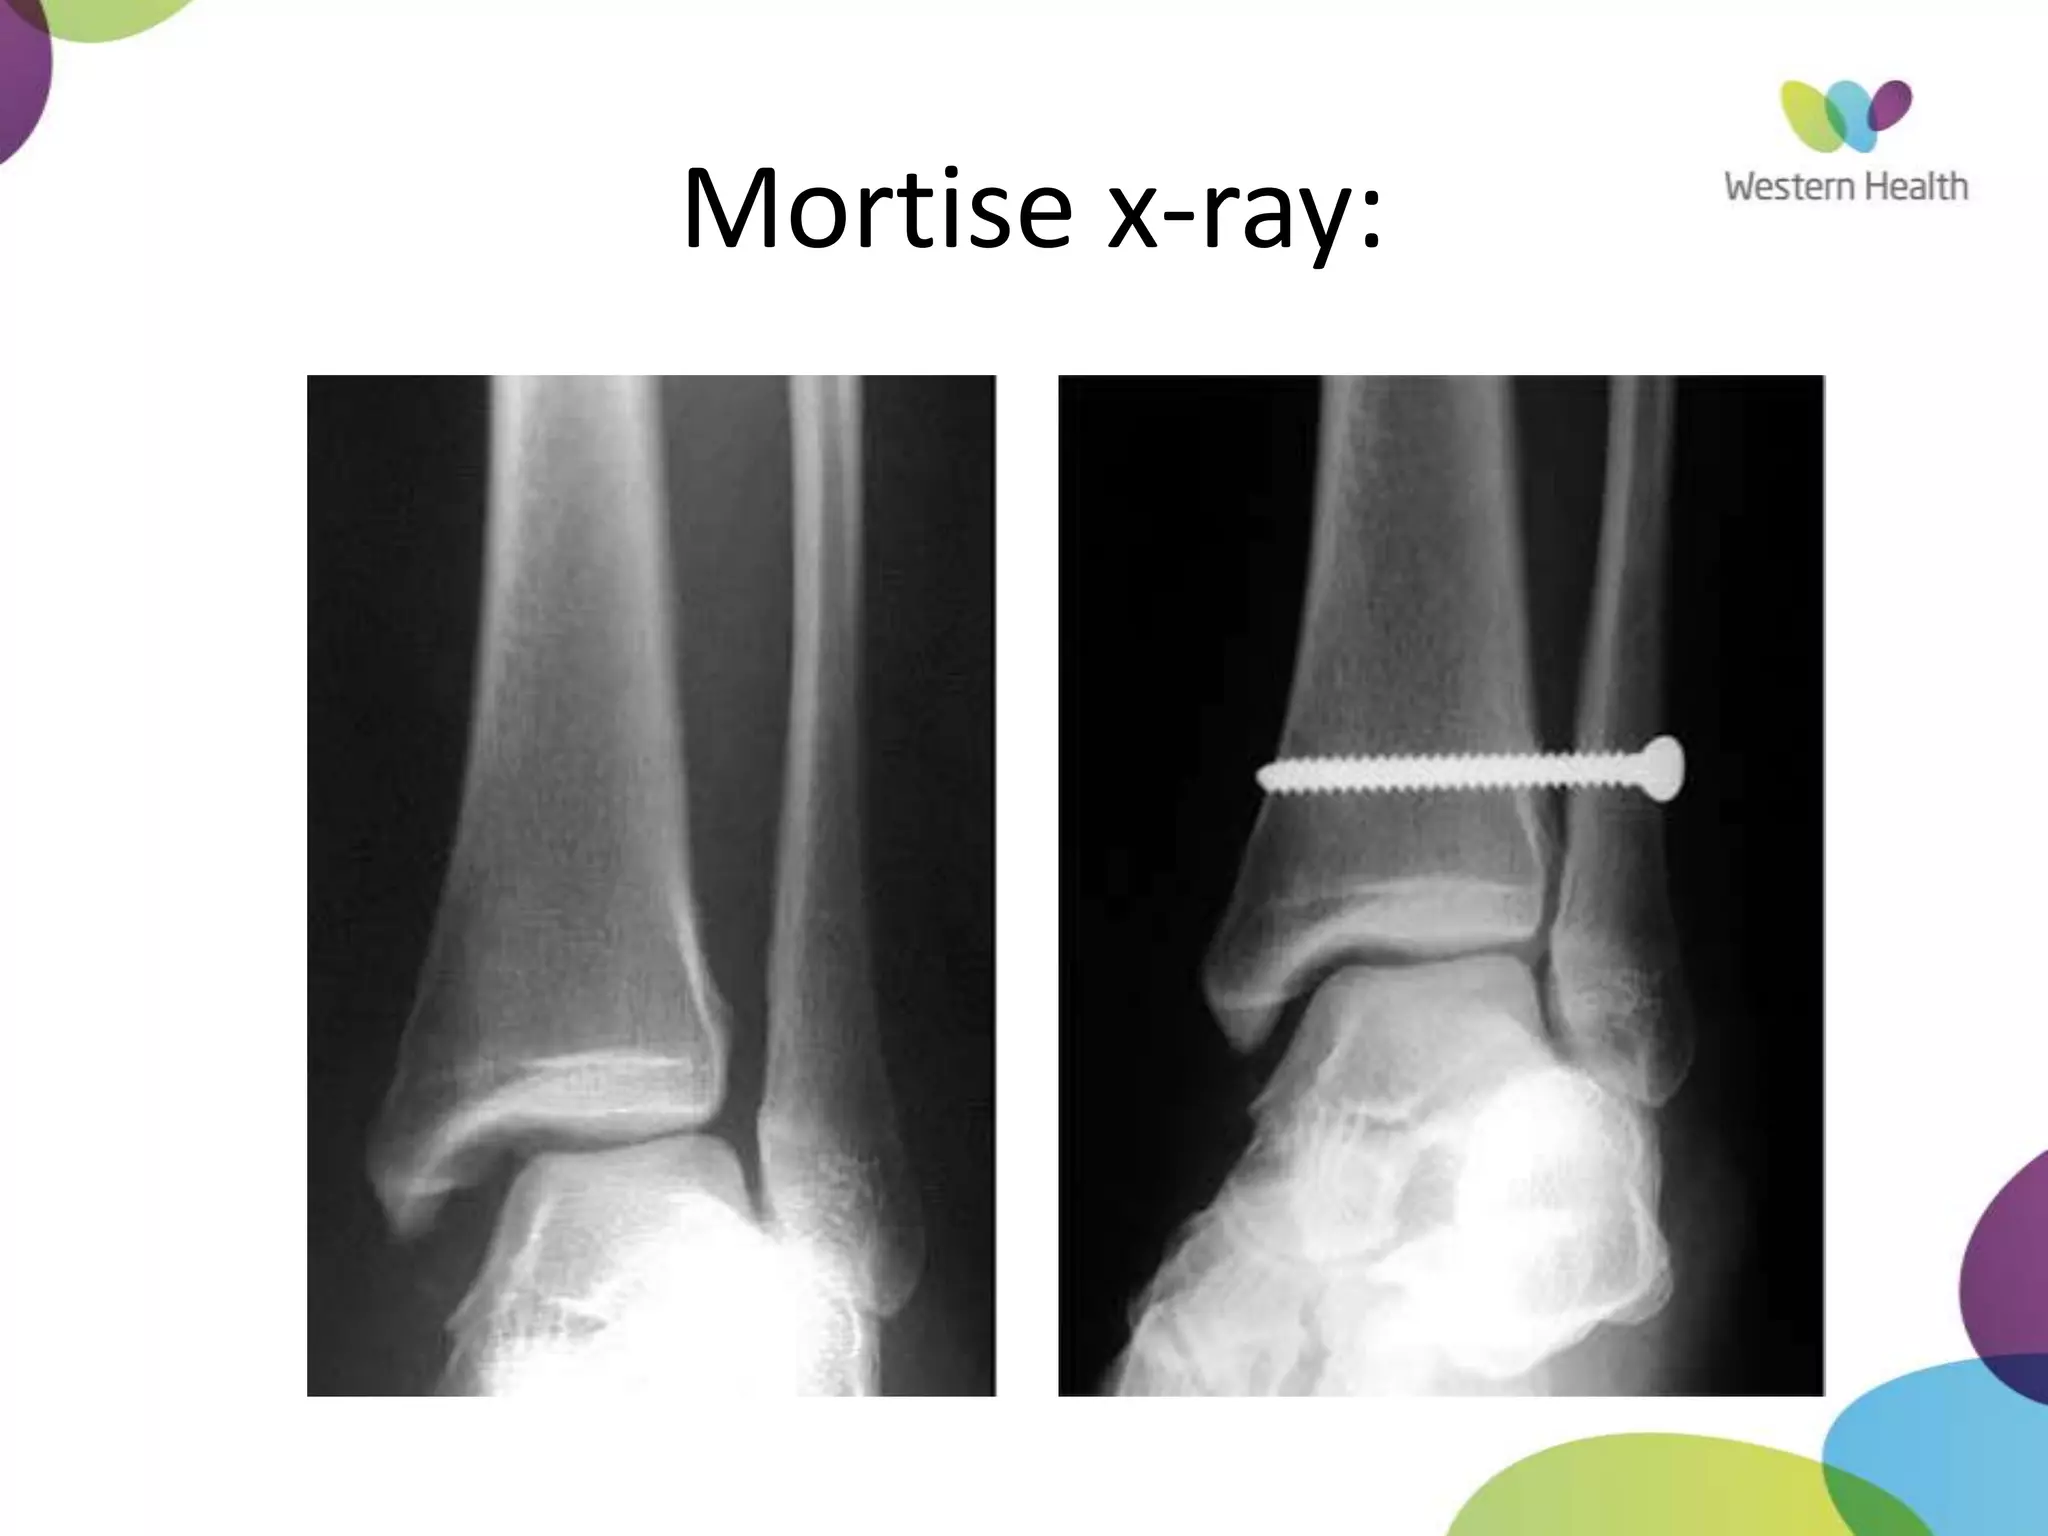

Mortise X-Ray

• ankle in 15-25° of IR

• Medial clear space

– Between lateral border of

medial malleous and medial

talus

– <4mm is normal

– >4mm suggests lateral shift

of talus

Mortise x-ray: